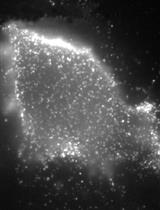

Metastasis depends on a gene program expressed by the tumor microenvironment upon TGF-beta stimulation. CRC (Colorectal cancer) cell lines did not induce robust stromal TGF-beta responses when injected into nude mice as shown by lack of p-SMAD2 accumulation in tumor-associated stromal cells. To enforce high TGF-beta signaling in xenografts, we engineered CRC cell lines to secrete active TGF-beta. Subcutaneous tumors obtained from HT29-M6TGF-β, KM12L4aTGF-β cells and SW48TGF-β cells contained abundant p-SMAD2+ stromal cells.

Figure 1. p-SMAD2 staining (arrowhead) in liver metastasis generated after intrasplenic injection of CRC cells. E: epithelial cells, Str: stromal cells. Scale bars = 10 μm